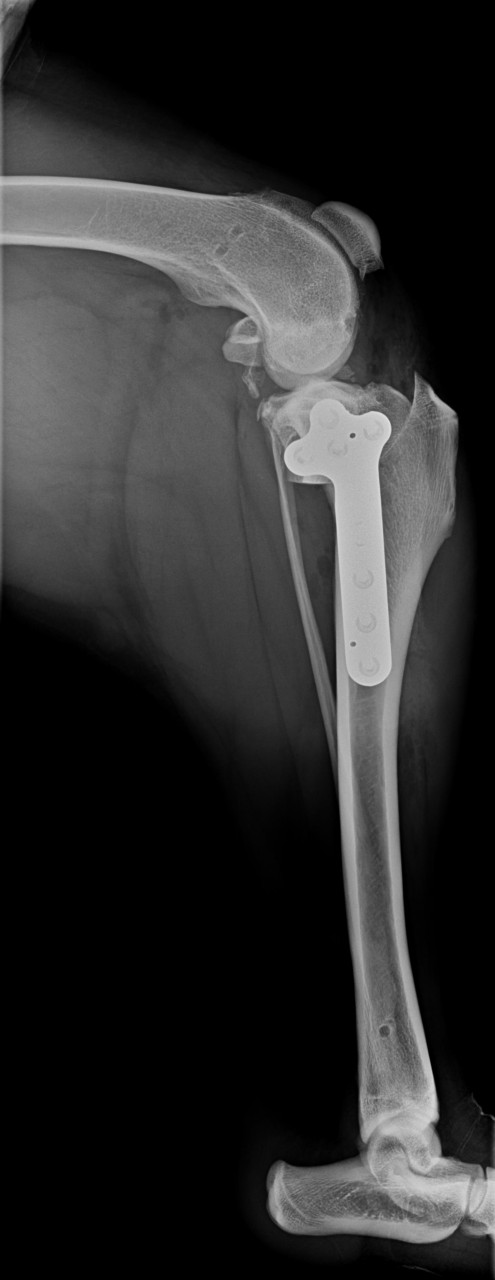

Falls es wenn interessiert das sind die Röntgenbilder von der OP.

Da oben wo man die kleine Ecke sieht, hat man den Schienbeinkopf zersägt und gedreht